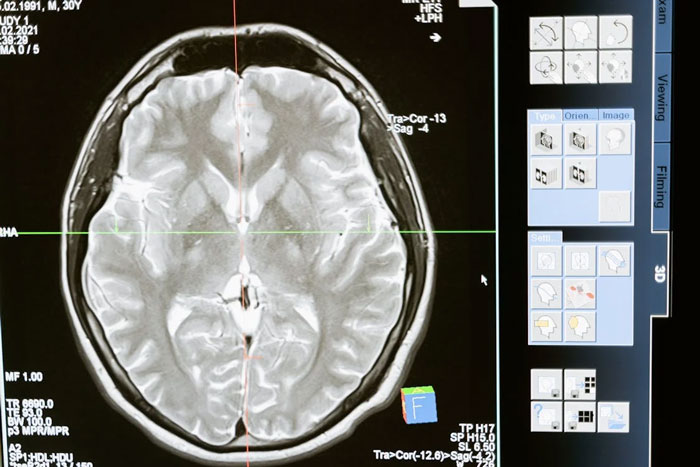

A friend told me that humans only use 10% of their brains and that unlocking the other 90% could give you superhuman abilities. Turns out, we use pretty much all of our brain, just not all at once.